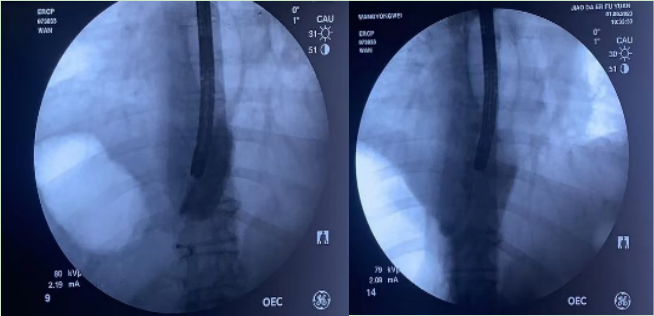

经过充分的准备,在消化内科王进海主任的支持及指导下,患者由手术经验丰富的万晓龙副教授和杨龙宝博士对食管曲张静脉进行透视下精准硬化治疗,操作由郭晓丹、秦赟、李婵三位护士配合。进镜后,自食管上段至贲门可见4条纵行食管曲张静脉,最大直径1.5cm,红色征阳性。选取食管左侧壁食管曲张静脉作为注射点,食管球囊充气后,对食管曲张静脉进行造影剂+硬化剂注射,透视下可见造影剂及硬化剂充盈食管曲张静脉并向下延续,注射部位渗血,球囊压迫3分钟后出血停止。再次选取食管右侧壁食管曲张静脉进行注射,重复上述过程,可见造影剂及硬化剂充盈食管曲张静脉及胃左静脉前支。再次用胃镜观察,可见硬化的食管曲张静脉扁平,局部黏膜发白,达到预期疗效。

内镜下硬化技术作为肝硬化食管静脉曲张治疗的主要手段之一,在临床上广泛应用。胃左静脉前支作为食管曲张静脉的主要来源血管,理论上只有保证硬化剂充分填充食管曲张静脉及胃左静脉前支,才能实现消除食管静脉曲张,达到“精准硬化”的目的。目前临床上常用的内镜下硬化技术多采取盲打的方法,复发率较高,且难以实现“精准硬化”的目的。此次消化内科实施的透视下精准硬化术与传统硬化不同的是,操作过程需要借助X线及食管球囊的辅助,通过硬化剂及造影剂的联合应用,可以保证硬化剂充分填充食管曲张静脉及其来源血管,食管球囊的应用,有助于稳定镜身、对出血部位压迫止血,减少造影剂逆流进入纵膈引起肺栓塞等严重并发症的风险,大大提高了手术的安全性。